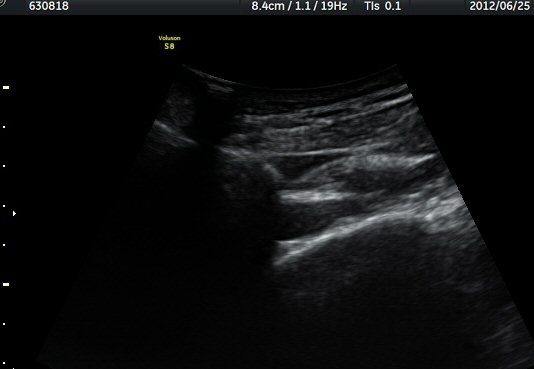

ÃÊÀ½ÆÄ °Ë»ç

¾î±ú °üÀý µÚÂÊ ÈĹæ°üÀý¼ø Ⱦ´Ü¸é°Ë»ç¿¡¼­ °üÀý¼ø ³»Ãø, °¡½Ãµ¹±â°üÀý¼ø°í¶û(spinoglenoid

notch)¿¡¼­ Àú¿¡ÄÚ ³¶Á¾ÀÌ °üÂûµÈ´Ù(±×¸² 1). ŽÃËÀÚ¸¦ À§-¾Æ·¡ ¹æÇâÀ¸·Î º¯°æÇÏ¿© °üÂûÇÒ ¶§µµ

¿ª½Ã °ß°©°ñ °¡½Ãµ¹±â(spine) ¾Æ·¡¿¡¼­ Àú¿¡ÄÚ ³¶Á¾ÀÌ °üÂûµÈ´Ù(±×¸² 2). º¼·ÏŽÃËÀÚ·Î ¹Ù²Ù¾î °ü

ÂûÇÏ´Ï  °¡½Ãµ¹±â°üÀý¼ø°í¶û¿¡¼­ Àú¿¡ÄÚ ³¶Á¾ÀÌ ´õ¿í ¶Ñ·ÈÈ÷ °üÂûµÈ´Ù(±×¸² 3, 4).